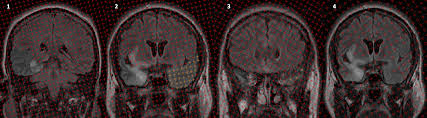

Herpes simplex (hsv) encephalitis is the most common cause of fatal sporadic fulminant necrotizing viral encephalitis and has characteristic imaging findings. Metabolic, vascular, neoplastic, infective and paraneoplastic diseases. A 40‑year‑old male patient with herpes simplex virus encephalitis presented with altered sensorium. Key imaging features include bilateral or unilateral signal abnormality in the temporal lobes that extends to the limbic system, early hemorrhagic changes, restriction on dwi, and abnormal enhancement. Mri revealed hyperintensities on t2 weighted images in both frontal and temporal lobes suggestive of herpes simplex encephalitis (fig 1).

A feasibility study of quantifying longitudinal brain changes in herpes simplex virus (hsv) encephalitis using magnetic resonance imaging (mri) and stereology. In the present study, flair bth was most frequently seen in patients with hsv encephalitis. Mri is the diagnostic modality of choice abnormal in 90%; Herpes simplex virus (hsv) encephalitis hsv encephalitis (hsve) is the most common cause of infectious encephalitis (1); The basal ganglia are usually spared. Encephalitis, magnetic resonance imaging, meningoencephalitis, viral. that appeared in a recent issue of clinical infectious diseases. Although far less common, essentially any part of the central nervous system can be involved 9. 1 mri t2 weighted image, showing bilateral temporal lobe hyperintensities. However, mimics of hse, including other infections and increasingly recognized autoimmune causes, have been described in cases of tl encephalitis. Two subtypes are recognized which differ in demographics, virus, and pattern of involvement. Because early diagnosis is possible in more cases of herpes simplex encephalitis (hse) as a result of the high sensitivity of mri, now widely available, a larger number of patients are receiving appropriate treatment with iv acyclovir. Limbic encephalitis, mca ischaemia, tumours, effects of seizures) hyperintense t2 signal in the medial temporal lobes, inferior frontal lobes and insula basal ganglia are usually spared

We describe the spectrum of etiologies associated with temporal lobe (tl) encephalitis and identify clinical and radiologic features that distinguish herpes simplex encephalitis (hse) from its mimics. In addition, it was observed in various pathological conditions: A feasibility study of quantifying longitudinal brain changes in herpes simplex virus (hsv) encephalitis using magnetic resonance imaging (mri) and stereology. Encephalitis, magnetic resonance imaging, meningoencephalitis, viral. In the present study, flair bth was most frequently seen in patients with hsv encephalitis. that appeared in a recent issue of clinical infectious diseases. 1 mri t2 weighted image, showing bilateral temporal lobe hyperintensities. A brain biopsy was performed and the histology was consistent with encephalitis.